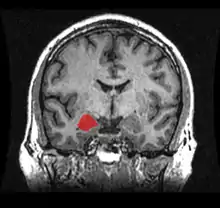

The amygdala (/əˈmɪɡdələ/; plural: amygdalae /əˈmɪɡdəli, -laɪ/ or amygdalas; also corpus amygdaloideum; Latin from Greek, ἀμυγδαλή, amygdalē, 'almond', 'tonsil'[1]) is one of two almond-shaped clusters of nuclei located deep and medially within the temporal lobes of the brain's cerebrum in complex vertebrates, including humans.[2] Shown to perform a primary role in the processing of memory, decision making, and emotional responses (including fear, anxiety, and aggression), the amygdalae are considered part of the limbic system.[3] The term "amygdala" was first introduced by Karl Friedrich Burdach in 1822.[4]

![]() Location of the amygdalae in the human brain | |